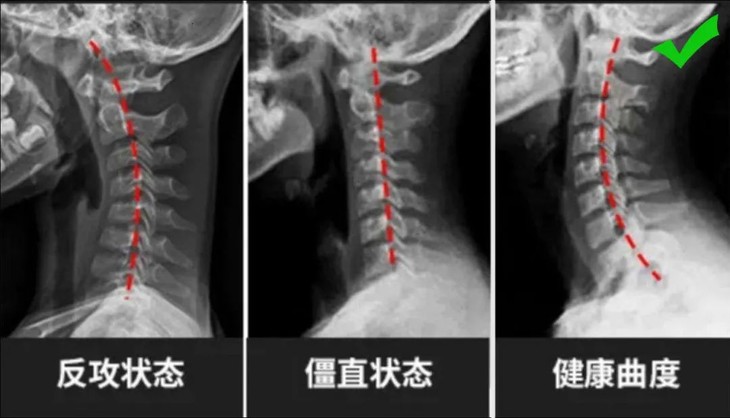

医生说,颈椎有一个圆滑的,朝向前方的弧,这是生理曲线,但是现在人们的不当姿势,就会引发颈椎变形!

这就是肩颈酸疼,失眠多梦,头晕眼花的罪魁祸首!

最好的办法就是,用枕头帮助人体维持颈椎正常弧度!